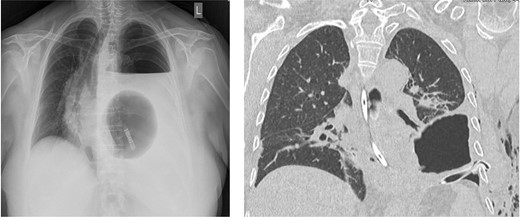

One day after admission, the patient developed massive dyspnea with a rapid deterioration of general condition. Chest X-ray showed a large left-sided tension seropneumothorax with a right-sided mediastinal shift (Fig. 2). Uncomplicated, ultrasound-guided chest drain insertion was performed immediately, and the clinical condition improved instantly. However, gastric secretion through the chest tube was observed and gastric perforation as a cause for the seropneumothorax was suspected. Therefore, emergency surgery was performed. A lift-sided antero-lateral thoracotomy was performed to rule out any lung parenchym lesions. Intraoperatively, a 2 × 2 cm gastric perforation was found (Fig. 3). After excision, the perforation was sutured, and the stomach was transposed into the intraabdominal cavity. Fibro-purulent empyema (stage II) was observed and local pleurectomy and decortication of the left lower lobe were performed. A transverse upper laparotomy was performed. After adhesiolysis due to massive adhesions following previous surgeries, hernia sac was excised, mobilization of the esophagus was carried out and crura were closed. Due to the present infection, no alloplastic material was used. A partial Watson anterior wrap was performed. There were no intraoperative complications. The patient was extubated in the operation room and transferred to the intermediate care unit for further observation. The postoperative course was uneventful, and patient was discharged in good condition on POD 7. Histological examination revealed a Helicobacter-positive gastric ulcer as a cause for gastric perforation. Two months after discharge, gastroscopy was performed and showed a normal finding with no signs of recurrence of the hiatal hernia.

Chest X-ray showing a large left-sided tension seropneumothorax with a right-sided mediastinal shift. Chest CT-scan after insertion of a chest tube.